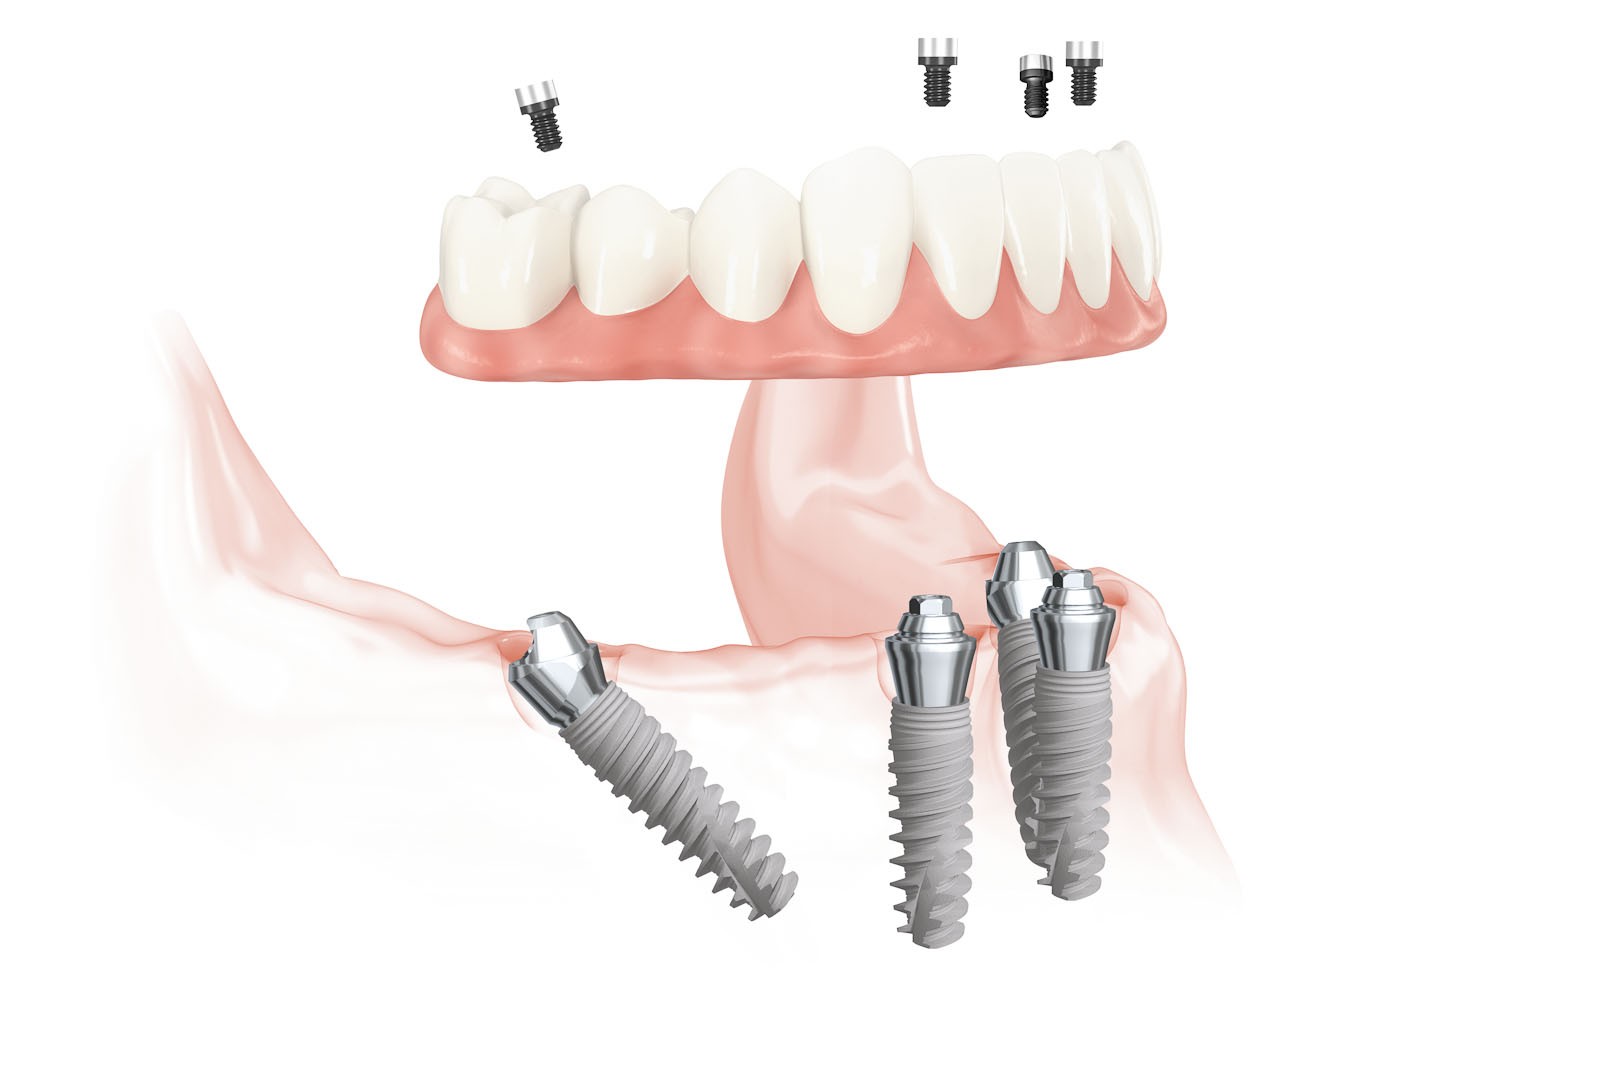

- ALL-ON-4 to sprawdzona i przewidywalna metoda odbudowy uzębienia na implantach dla bezzębnych pacjentów. To opatentowany system rehabilitacji opartej na 4 wszczepionych implantach, gdzie 2 środkowe są wprowadzone równolegle, 2 skrajne – skośnie, pod kątem 45 stopni.

- Poprzez użycie pochylonych implantów w odcinkach bocznych pozwala uniknąć uszkodzenia ważnych szczegółów anatomii oraz zwiększa powierzchnię przylegania i osteointegracji implantów z kością.

- Rozwiązania protetyczne w systemie all-on-4 uwzględniają możliwość wykonania stałych prac protetycznych, czyli mostów zamocowanych na stałe, jak również protez ruchomych wspartych jedynie na implantach.

- System umożliwia natychmiastowe obciążenie implantów tymczasowym mostem protetycznym zaraz po założeniu implantów.

Na implantach wszczepionych zgodnie z protokołem all-on-4 możliwe są do wykonania stabilne mosty, jak również ruchome protezy typu nakładowego. Uproszczenie i optymalizacja rozwiązań protetycznych możliwa jest dzięki zastosowaniu kątowych łączników typu MultiUnit (17°, 30°), które po przykręceniu do pochylonych implantów umożliwiają łatwe mocowanie mostu i obsługę serwisową pacjenta.

- ALL-ON-4 to sprawdzona i przewidywalna metoda odbudowy uzębienia na implantach dla bezzębnych pacjentów. To opatentowany system rehabilitacji implantoprotetycznej oparty na 4 wszczepionych implantach, gdzie 2 środkowe są wprowadzone równolegle, 2 skrajne – skośnie, pod kątem 45 stopni.

Jest to opatentowana metoda rekonstrukcji implanto-protetycznej kompletnego uzębienia stosowana przy bezzębiu zarówno dla dolnego, jak i górnego łuku zębowego. Bazuje na charakterystycznie wszczepionych 4 implantach zębowych, stąd nazwa Wszystko na 4. Dwa środkowe wprowadzane są w kość prostopadle do jej brzegu i równolegle do siebie, dwa boczne wszczepiane są pod kątem 45 stopni. Rozwiązanie protetyczne to most przykręcany na stałe do implantów, który może być zakładany natychmiast po zabiegu implantacji lub w czasie odroczonym. Gwarancją natychmiastowego przywrócenia funkcji żucia jest odpowiednia siła osadzania implantów mierzona dynamometrycznie w trakcie ich wszczepiania oraz należyta staranność wykonania i osadzenia prac protetycznych.